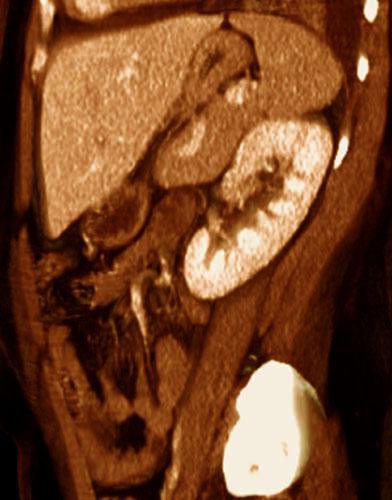

Pielonefritis aguda 2